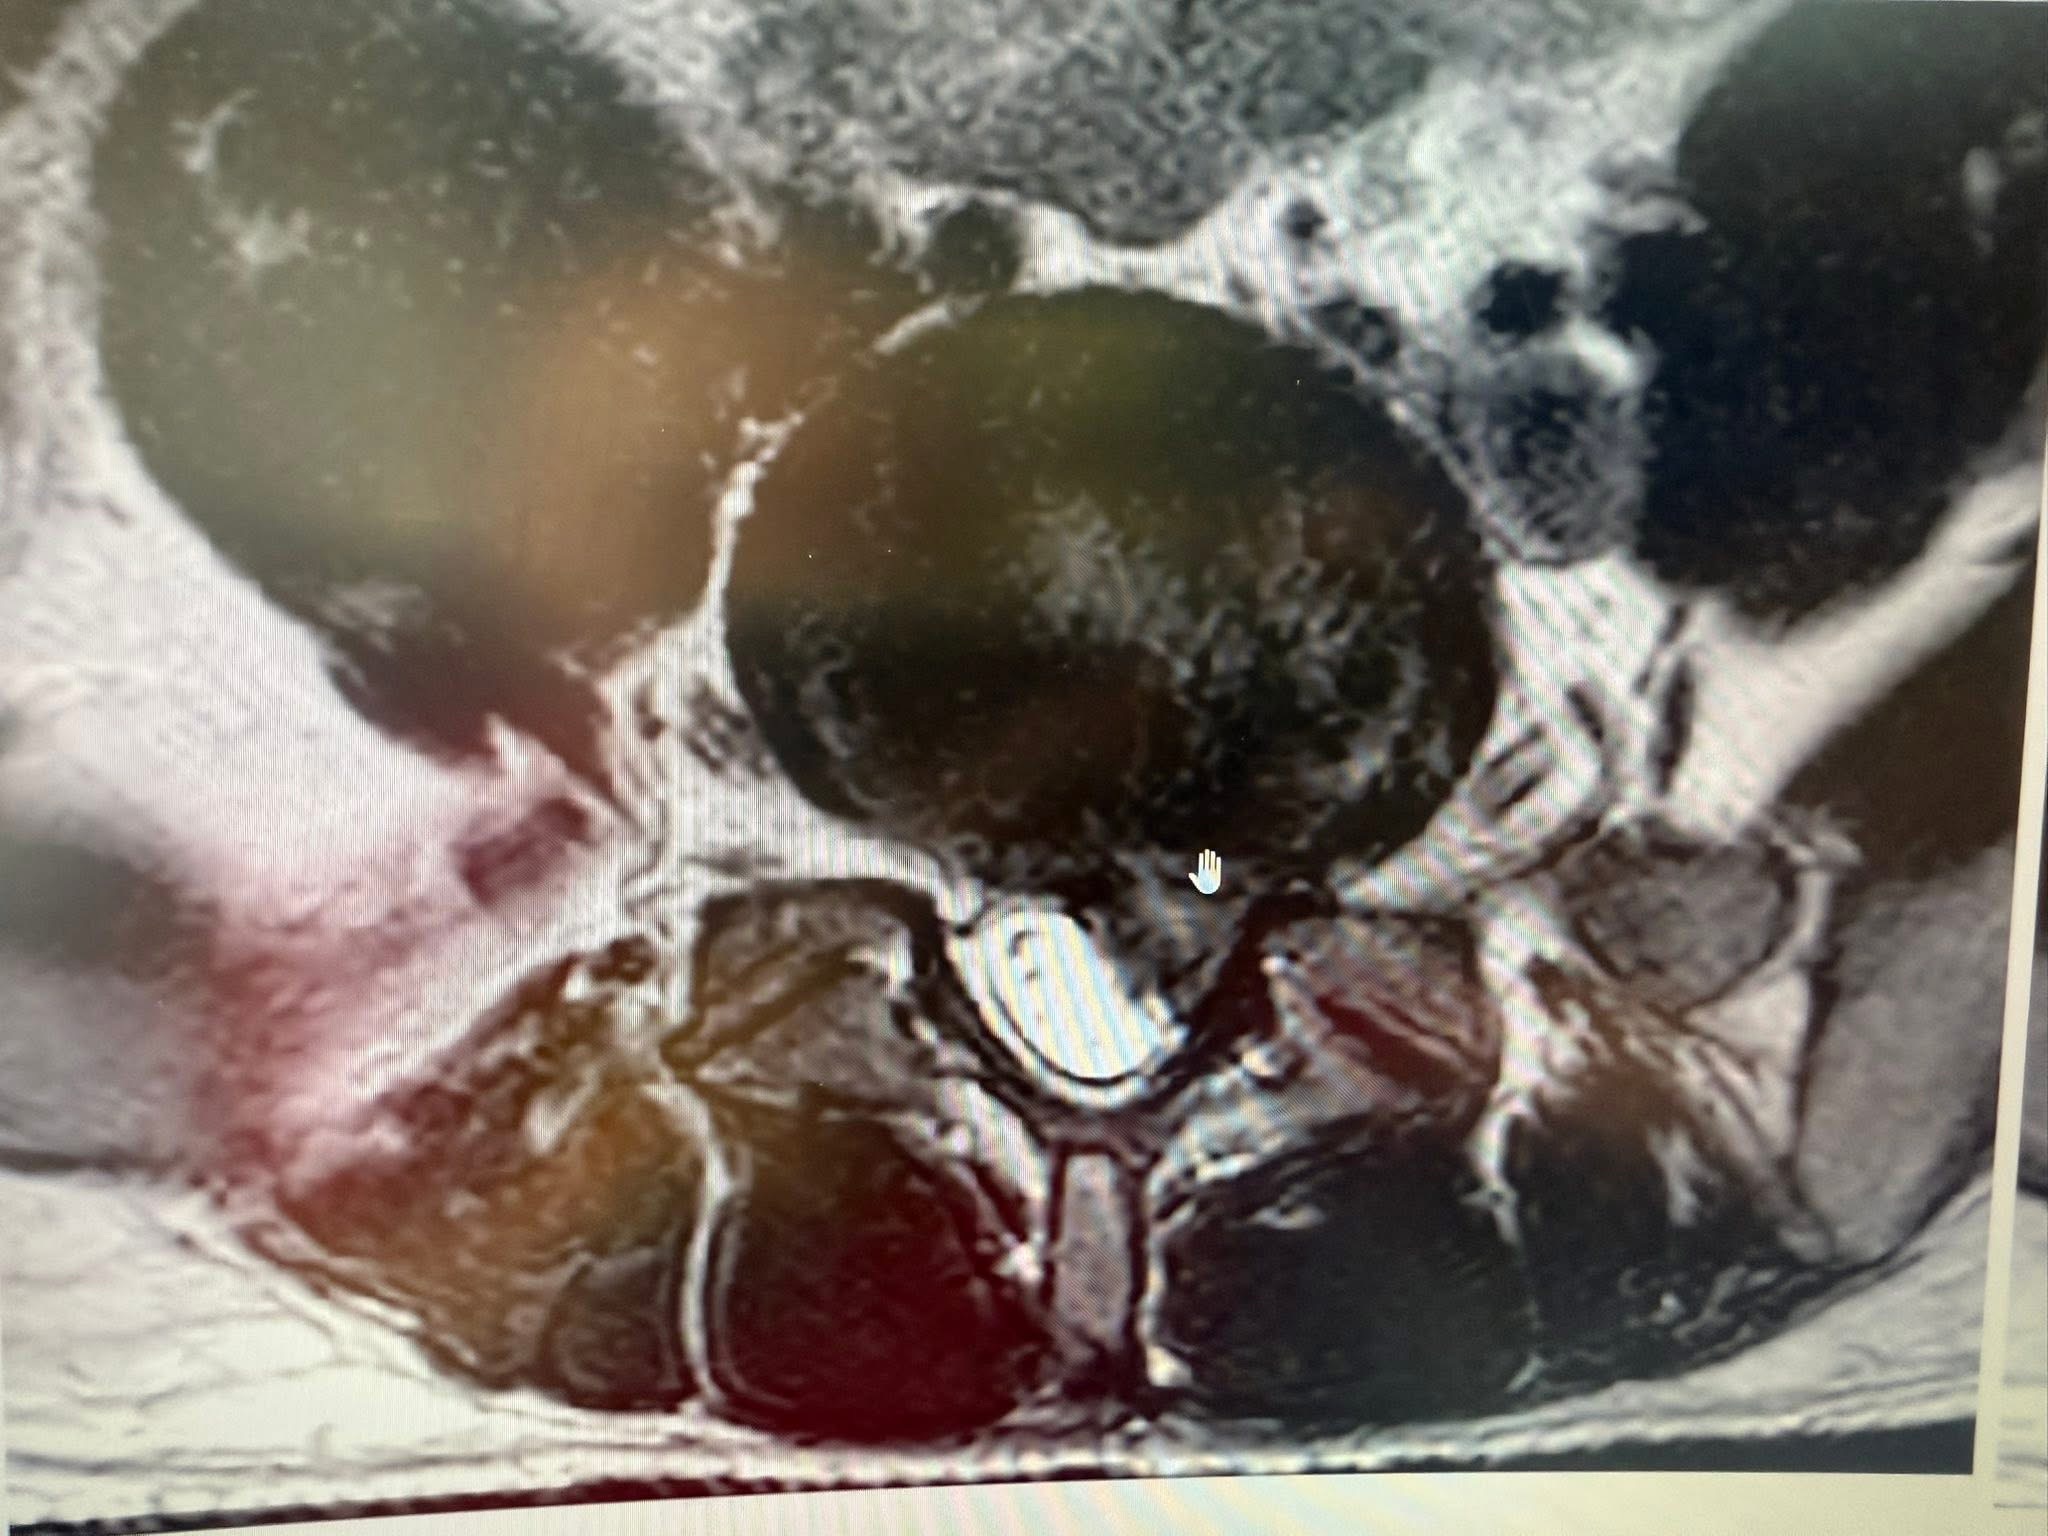

經詳細詢問病史,他患有L5/S1巨大椎間盤突出,導致左側坐骨神經嚴重壓迫,出現典型的「痠、麻、脹、痛、跛行」。過去兩個月,他已在在地復健科接受常規治療——熱敷、電療、牽引——但效果不彰,甚至一度惡化。

• 針刀針對L5/S1關鍵椎間孔位進行「空間引導」,使突出的髓核減壓、神經恢復生理傳導

感想:脊椎整合中醫微創療法可能是在關節面跟惻隱窩減壓,讓椎間盤內的高壓下降,搭配針灸刺激多裂肌與核心肌群的增生,讓脊上韌帶恢復力量,對抗椎間盤突出,自然提供一個很好髓核自行吸收的環境。